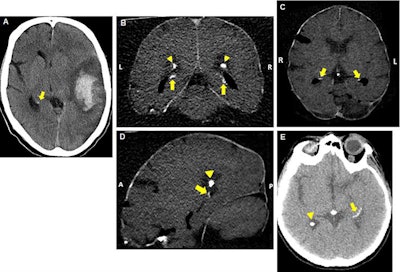

Though calcifications in the hippocampus are common, especially for seniors, little is known about their risk factors and effect on memory, partly due to the frequent misidentification of calcifications in the hippocampus as calcium buildup in the choroid plexus and vice versa, de Brouwer said. Recently, technological advancements in CT scanning have provided clinicians with improved visualization of calcifications in these small brain structures.

A total of 380 (19.1%) patients had hippocampal calcifications on their CT scans based on a reading by one of two trained physicians. The physicians rated each case based on the highest degree of calcification -- absent, mild, moderate, or severe -- with "good" interobserver agreement between the readers.